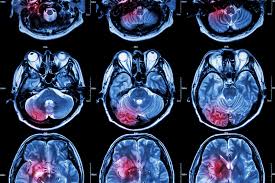

A brain scan is not performed just to confirm that an injury exists. It is used to detect conditions that can worsen quickly or cause permanent damage if left untreated, such as bleeding, swelling, or structural injury to the brain.

Types of Brain Scans Commonly Used

Doctors typically rely on two types of imaging after head trauma.

CT scans are usually the first step in emergency settings. They are fast and effective at identifying bleeding, skull fractures, and life-threatening conditions.

MRI scans are more detailed and often used when symptoms persist. MRIs are better at detecting subtle brain injuries, including diffuse axonal injury, which may not appear on a CT scan.